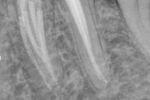

Revisionsbehandlung eines Unterkiefermolaren (37) vor geplanter Überkronung (Dr. Maik Göbbels) Download